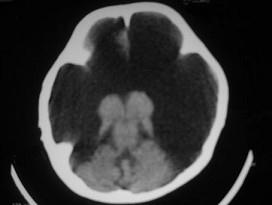

问题 女,1岁半,头颅迅速增大,行CT检查如图,请选出最可能的诊断 ( )

选项 A、硬膜下积液 B、脑内血肿 C、硬膜外血肿 D、硬膜下血肿 E、积水型无脑畸形

答案 E